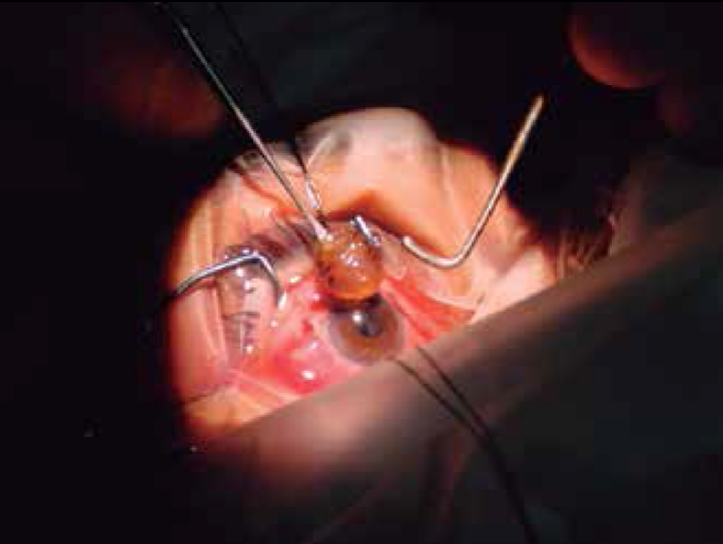

Lentes Intraoculares Suturada a Sulcus Visioncore Cl nica outlet, Reposicionamiento intercambio de lentes intraoculares outlet, Qu son los lentes intraoculares Como Cuidar Los Ojos outlet, Implante de una Lente Intraocular Multifocal M PLUS outlet, Visian ICL lentes intraoculares f quicas outlet, Cirug a Presbicia lentes intraoculares Hospital Universitari outlet, Tipos de lente intraocular en la cirug a de catarata Cl nica outlet, Lente intraocular f quico cirug a que permite dejar de usar outlet, Lentes ICL o Lentes Intraoculares Ventajas e Indicaciones outlet, LENTES INTRAOCULARES Centro de Ojos Buenos Aires outlet, Implante de lentes intraoculares todo lo que debes saber outlet, Todos sobre la operaci n de cataratas con lente intraocular outlet, Cirug a refractiva con lentes intraoculares ICL rea Oftalmol gica outlet, Lentes intraoculares efectos secundarios y complicaciones Blog outlet, Lentes intraoculares para miop a outlet, Implantaci n de lente intraocular de c mara anterior outlet, Cirug a refractiva con lentes intraoculares Miranza outlet, Lentes intraoculares ICL en qu casos est n indicadas Blog D outlet, Cirug a refractiva con lentes pseudof quicas Instituto outlet, Centro Peruano del Pterigion Cirug a de CATARATA Implante de outlet, Cirug a refractiva con lentes intraoculares XR Oftalmolog a outlet, El Lente Intraocular se utiliza toda la vida Beneficios y Costo outlet, Cirug a refractiva con Lentes Intraoculares ICL en Madrid outlet, Lentes Intraoculares F quicas introducci n y complicaciones outlet, Cirug a refractiva con lentes intraoculares en Turqu a Tour for Cure outlet, Qu problemas pueden causar las lentes intraoculares outlet, Qu es una lente intraocular t rica outlet, CIRUG A CATARATA FACOEMULSIFICACION LENTE INTRAOCULAR outlet, Sorpresa refractiva por error en el c lculo de lente intraocular outlet, Precio de lentes intraoculares Operaci n de Ojos outlet, Lentes intraoculares LIO para cataratas premium asf ricas y outlet, Lente intraocular en qu consiste la operaci n y cu ndo se outlet, Lentes intraoculares en la cirug a de catarata Vista Instituto outlet, Implante de Lente Intraocular Dr Gabriel Oliveros outlet, Video Lentes intraoculares para la operaci n de miop a una outlet, Lentes intraoculares ajustables El futuro est aqu outlet, La cirug a de implante de lentes intraoculares para la presbicia outlet, Tras las lentes intraoculares m s de un 40 sufre cataratas a los outlet, Oftalmocentro San Javier outlet, Cirug a L ser Refractiva Lente Intraocular Visian ICL outlet, Sorpresa refractiva por error en el c lculo de lente intraocular outlet, Lente intraocular Cl nica oftalmol gica VISTA S nchez Tranc n outlet, Reemplazo de lente y la cirug a de las cataratas American outlet, Conoce todo sobre un lente intraocular Top Doctors outlet, Cirug a de Catarata Centro Oftalmol gico Doctores Adrogu outlet, El Hospital Mancha Centro empieza a implantar lentes intraoculares outlet, ACTUALIZACION EN LENTES INTRAOCULARES . Dra. Gloria Carretero Leon outlet, Lentes intraoculares f quicas outlet, EN QU CONSISTE LA CIRUG A DE CATARATA Instituto Oftalmol gico outlet, CAMPA A DE LENTES INTRAOCULARES ICL Vithas Eurocanarias outlet.

Cirugia de lentes intraoculares outlet